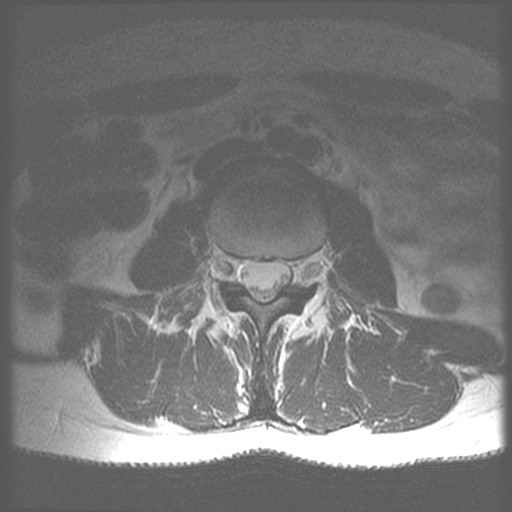

CWZ